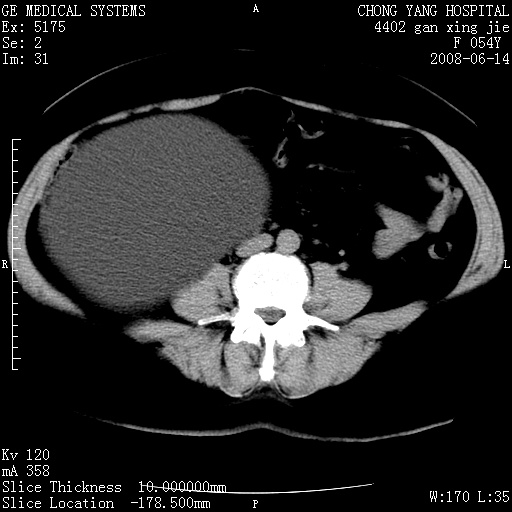

标题: CT14033:F54Y,来源哪? 外伤发现,自述既往无不适。 [打印本页]

标题: CT14033:F54Y,来源哪? 外伤发现,自述既往无不适。

1、脂肪肝。2、腹腔囊性占位,首考虑来源于右肾下极,其次考虑来源于肠系膜。

考虑肠系膜囊肿,脂肪肝

肠囊肿可能性大,与十二直肠水平部呈喇叭口,来源于十二直肠,不排除胰头假囊肿.

1、脂肪肝。2、腹腔囊性占位,首考虑肠源性囊肿或中肾管囊肿。

脂肪肝,来源于腹膜后囊肿可能性大。

脂肪肝,巨大肾囊肿

支持考虑肠系膜囊肿,脂肪肝.

考虑肠系膜囊肿

1)脂肪肝。2)右肾下极巨大囊肿。

右肾下极巨大囊肿可能性大。

右中下腹部囊性肿块,与右肾下极关系密切,考虑右肾下极巨大外生性囊肿;脂肪肝。